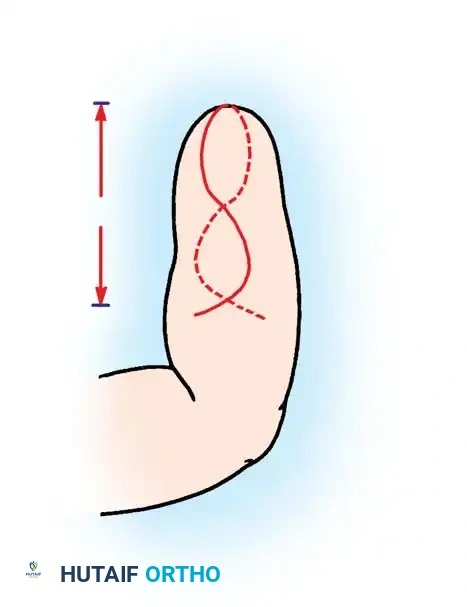

A newborn presenting with a transverse deficiency typically exhibits a slightly bulbous, well-padded stump. In more distal deficiencies, rudimentary, vestigial digital "nubbins" are frequently observed.

Fig. 76-2 Failure of formation (digital nubbins). The presence of functional wrist motion allows the limb to be used effectively as an assisting hand.

Hypoplasia of the more proximal musculature is a key clinical finding that helps differentiate true transverse deficiencies from amputations caused by congenital constriction band syndrome (amniotic band sequence). In the most common presentation—the upper forearm amputation—the forearm is usually no more than 7 cm long at birth and will reach a maximum length of approximately 10 cm by skeletal maturity.

In midcarpal amputations (the second most frequent level), the rudimentary digital remnants are almost always nonfunctional. However, because the radiocarpal joint is preserved, pronation and supination are usually possible, providing a highly functional assisting limb. Cognitive development and intelligence in these children are generally normal.